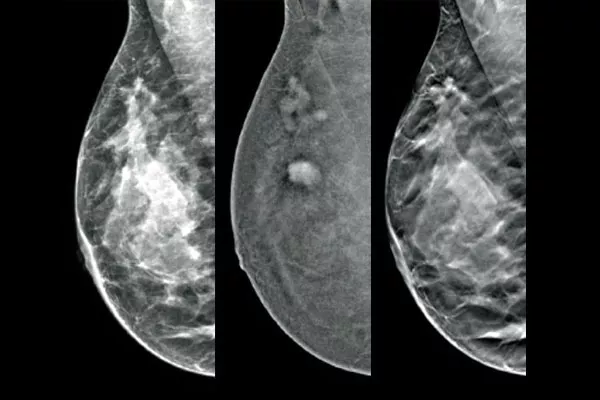

La solution de biopsie Affirm® avec contraste permet de cibler et de prélever du tissu mammaire dans les lésions identifiées lors d’une mammographie avec rehaussement de contraste (CEM). Conçue pour maximiser l’efficacité du flux de travail tout en améliorant le ressenti de la patiente, la solution complète de biopsie par contraste simplifie le processus de biopsie du sein*, même pour les procédures difficiles.

Cibler et effectuer la biopsie des lésions identifiées par la mammographie 2D avec rehaussement de contraste grâce à une procédure stéréotaxique, pour des performances diagnostiques comparables à l’IRM mammaire.1,2 Comparer les images post-marqueurs dans la même modalité que l’examen de contraste diagnostique initial.

Le logiciel Affirm de biopsie par contraste vous permet de biopsier les lésions identifiées pendant la mammographie 2D avec rehaussement de contraste I-View™. En tirant parti de la capacité à fournir des images 2D, des images avec rehaussement du contraste et des images de tomosynthèse sous une seule compression, 4le système de guidage pour biopsie mammaire en position verticale Affirm permet de passer rapidement du dépistage à la biopsie, en tirant parti de la même chaîne d’imagerie éprouvée5 que le système de mammographie pour améliorer la visualisation 3D™ des lésions suspectes.**

L’imagerie fonctionnelle, grâce à la CEM, est favorablement comparée à l’IRM mammaire avec une sensibilité similaire, une spécificité plus élevée et une valeur prédictive positive supérieure.7,8 La mammographie avec rechaussement de contraste constitue par ailleurs une alternative d’imagerie diagnostique rentable9 par rapport à l’IRM, avec une durée de procédure plus courte.7,10